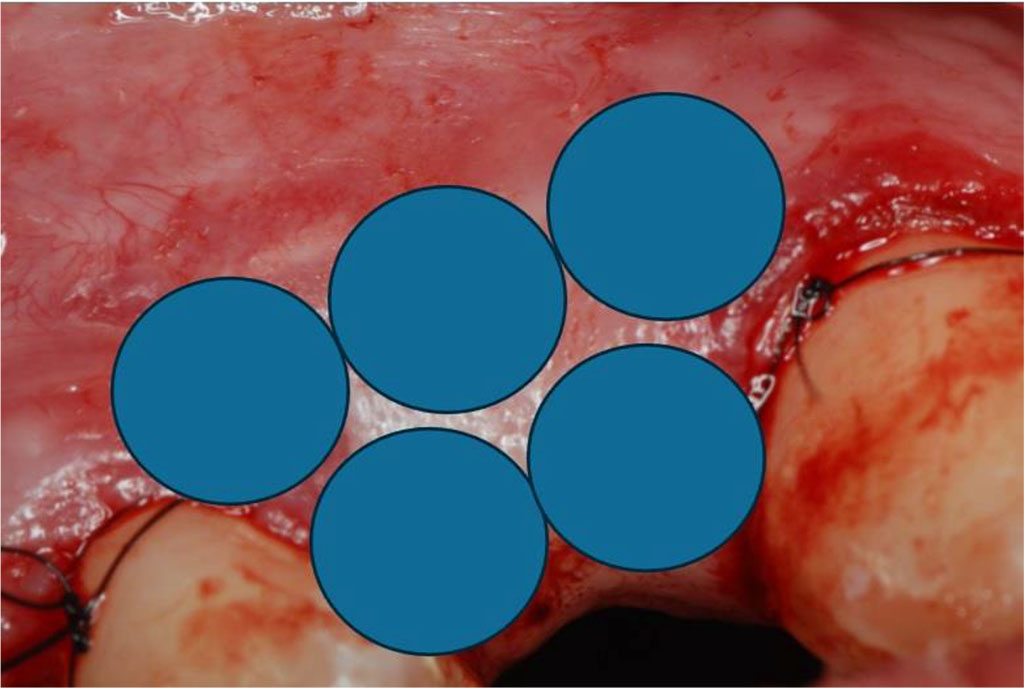

The patient, aged 42 was reffered from another dental office for peri-implant soft tissue augmentation in the aesthetic zone of the maxilla in the area of the implant located in position 13. Her history included type 2 diabetes, pharmacologically stabilised (she was taking Metformin 750mg twice a day), and no known allergies. Family history, no genetic burden. On extraoral clinical examination, no apparent facial asymmetry, chin and submandibular group A lymph nodes not palpable, not painful. Trigeminal nerve outlets not painful. No pathology in the temporomandibular joint. Intraoral clinical examination revealed a thin gingival biotype and a insufficient transverse gingival dimension in the vicinity of the implant at the crown neck of tooth 13, with no signs of inflammation, bleeding, bacterial plaque or pathological depths at the 6 points examined around the implant (Fig.1). The thickness of the keratinised gingiva at the implant at position 13 was measured by ultrasonography. The thickness of the keratinised gingiva was 0.75 mm (Tab.1). The width of the keratinized gingiva in the specified area was 1 mm (Tab.1).

Fig.1 The condition of the peri-implant soft tissues before sCTG augmentation.